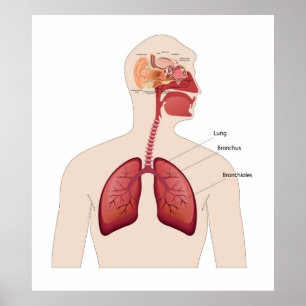

Póster O coração e as artérias bronquiais